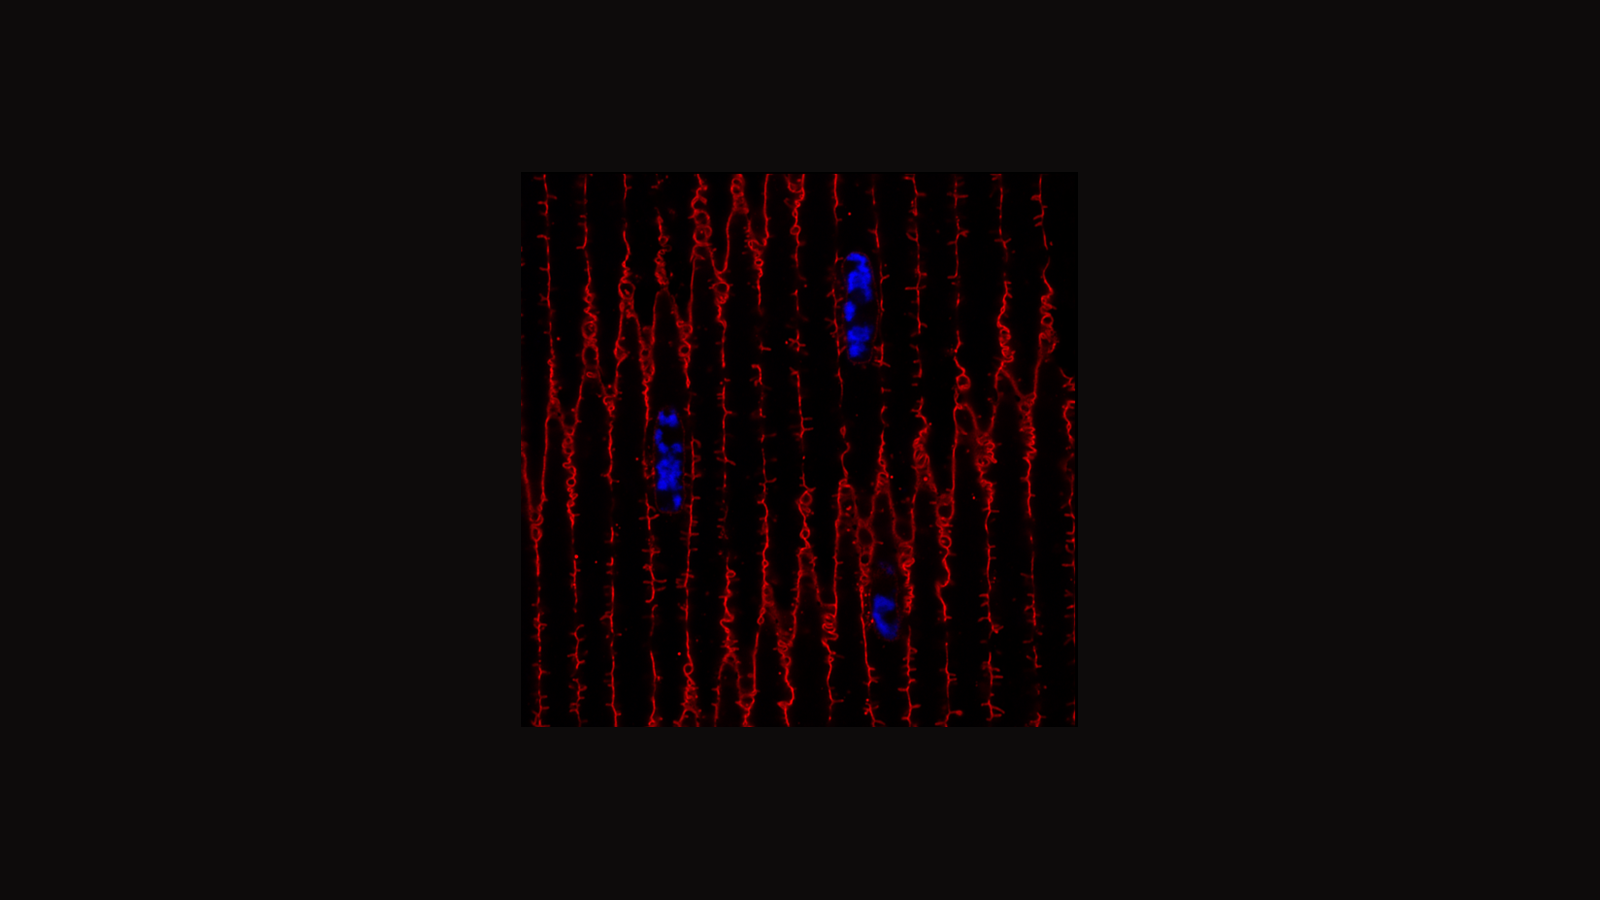

Confocal microscopy image of human heart, courtesy of Dr. Andrea Radtke of the Germain Lab at NIAID